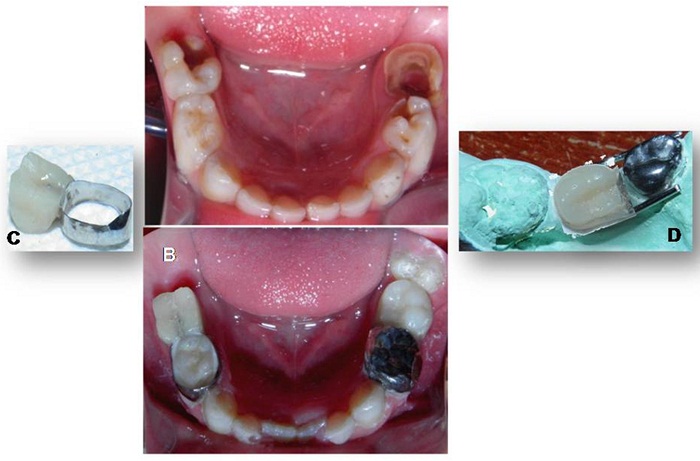

Para la elaboración del mantenedor de espacio se realizó una impresión con alginato en la arcada superior. Posteriormente, sobre el modelo en yeso, se diseñó un mantenedor de espacio removible sin flancos vestibulares y tornillo medio, para acompañar el crecimiento del maxilar. En el arco inferior se hicieron las exodoncias de los segundos molares, la pulpotomía del primer molar inferior derecho, con la adaptación de la corona de acero que se utilizaría como pilar del zapato distal derecho, y una restauración con resina en el primer molar izquierdo (figuras 5a y 5b). Antes de confeccionar los zapatos distales, se adaptaron la corona de acero en el primer molar inferior derecho y una banda con tubo en el primer molar inferior izquierdo (figuras 5c y 5d).

Esta última se adaptó ubicando el tubo hacia distal, a fin de utilizar esta porción como retenedor para el fantoche del segundo molar inferior izquierdo. Se tomó la impresión de arrastre para obtener los modelos de trabajo sobre los que se elaboraron los dos mantenedores de espacio tipo zapato distal propioceptivo. Luego de un correcto pulido, se cementaron con ionómero de vidrio 3M® (Ketac® Cem Easymix). Se indicó al paciente seguir una dieta blanda las primeras 2 horas después de la cementación, para evitar desadaptaciones del dispositivo, y una estricta higiene bucal. Los controles se efectuaron cada tres meses y, cuando erupcionaron los primeros molares permanentes, aproximadamente a los nueve meses, se utilizaron estos como pilares para confeccionar el arco lingual (figura 6).